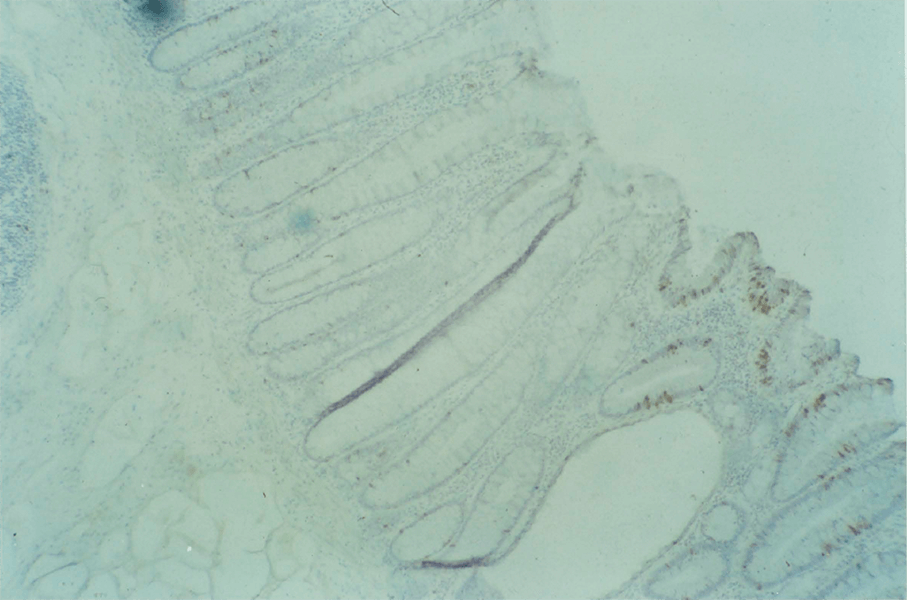

3:3. Photomicrograph of BRdU labelled colonic mucosa.

3:4. Photomicrograph of a BRdU labelled villous adenoma.

3:5. Photomicrograph of BRdU labelled colonic mucosa from a patient with polyposis coli.

3:6. Photomicrograph of labelled colonic mucosa from a patient with polyposis coli